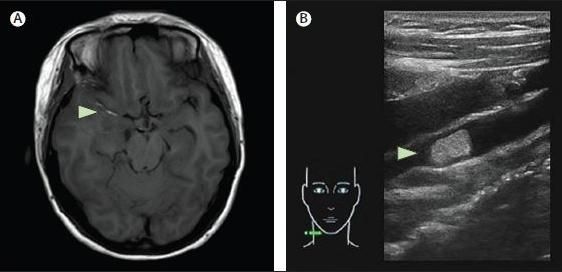

一位35歲女性,因“左側(cè)肢體乏力麻木25小時”入院。該患者在某美容院行“左側(cè)大腿內(nèi)側(cè)抽脂+面部自體脂肪填充術(shù)”時出現(xiàn)左側(cè)肢體偏癱、麻木。入院查體:左上肢肌力1級,左下肢肌力3級。頭顱CT示右側(cè)額島葉、基底節(jié)、放射冠區(qū)梗死,并可見右側(cè)大腦中動脈走形區(qū)低密度影,CTA發(fā)現(xiàn)右側(cè)大腦中動脈M1段閉塞。頸動脈CTA示右側(cè)頸內(nèi)、頸外動脈起始段見低密度充盈缺損影。頸動脈彩超示右側(cè)頸總動脈分叉處至頸內(nèi)及頸外動脈起始部可見高回聲的栓子形成。頭顱MR示右側(cè)大腦中動脈在T1像和T2像均發(fā)現(xiàn)高信號栓子影。該患者診斷為脂肪栓塞致急性腦梗死。予以藥物及康復(fù)等治療,患者癥狀好轉(zhuǎn)出院。